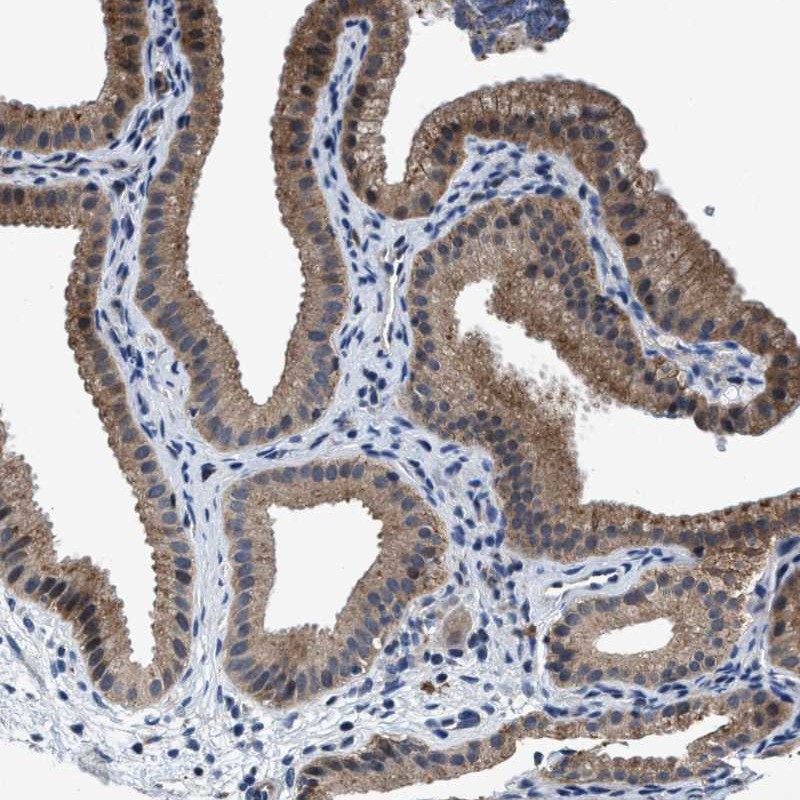

Immunohistochemical staining of human gallbladder shows moderate cytoplasmic positivity in glandular cells.